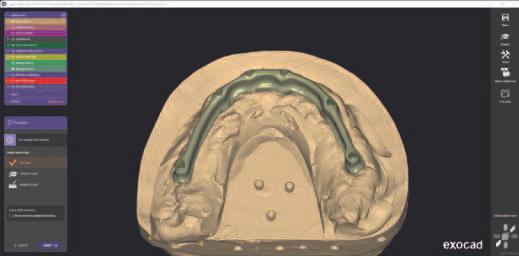

Supraprotezele ex stente poz ț onate în relaț a ocluzală curentă a pac ente ș apo crestele edentate au fost d g tal zate (f g. 4). Zona de proecț e pe modelele dentare analogce a fost decupată pentru a ajuta la montarea d g tală încruc șată. Acest lucru perm te capturarea nformaț -

lor despre creasta edentată în ceea ce pr vește relaț a ș d mens unea vert cală ș transferul acestor nformaț în so ware-ul de pro ectare as stată de calculator (computer-aded des gn, CAD) (f g. 5). În acest caz, a fost folos t un modul so ware pentru proteze dentare pentru a crea o nouă setare d g tală ce poate f t păr tă în scopur d agnost ce (f g. 6). Atașamentele ex stente ale m n - mplantur lor ar f preluate drect în cab net folos nd mater alul rad opac react v la cald; acest lucru ar perm te o tehn că duală de scanare CBCT pentru a fac l ta setarea d agnost că în plan f carea mplantur lor. Scopul no setăr este de a testa d fer te aranjamente dentare, de a reduce expunerea g ng vală ș de a ver f ca spaț ul restaurator d spon b l pentru a as gura un plan de reab l tare prec s, deoarece acest lucru ar putea afecta poz ț a ș d str buț a mplantur lor.

În cazul de față, s-a pro ectat o nouă setare restaurat vă folos nd ca refer nță restaurăr le ex stente ale supraprotezelor. Noua setare a fost apo t păr tă folos nd o mpr mantă 3D. Un f ș er separat a fost exportat d n so ware, ceea ce a perm s mpr mante să t părească baza folos nd răș nă transparentă. Setarea dentară t păr tă a fost l p tă pe baza transparentă. Această nouă setare a fost testată în cav tatea orală. S-a evaluat relaț a d ntre zona cerv cală a setăr dentare ș creasta alveolară restantă. De asemenea, s-a determnat neces tatea une componente roz a restaurăr lor f nale (f g. 7).

6. Configurația nouă a restaurării creată folosind modulul de proteză CAD pe baza datelor colectate din supraproteza existentă. În aceast etapă, s-au modificat dimensiunea dinților și expunerea gingivală pentru a îmbunătăți estetica.